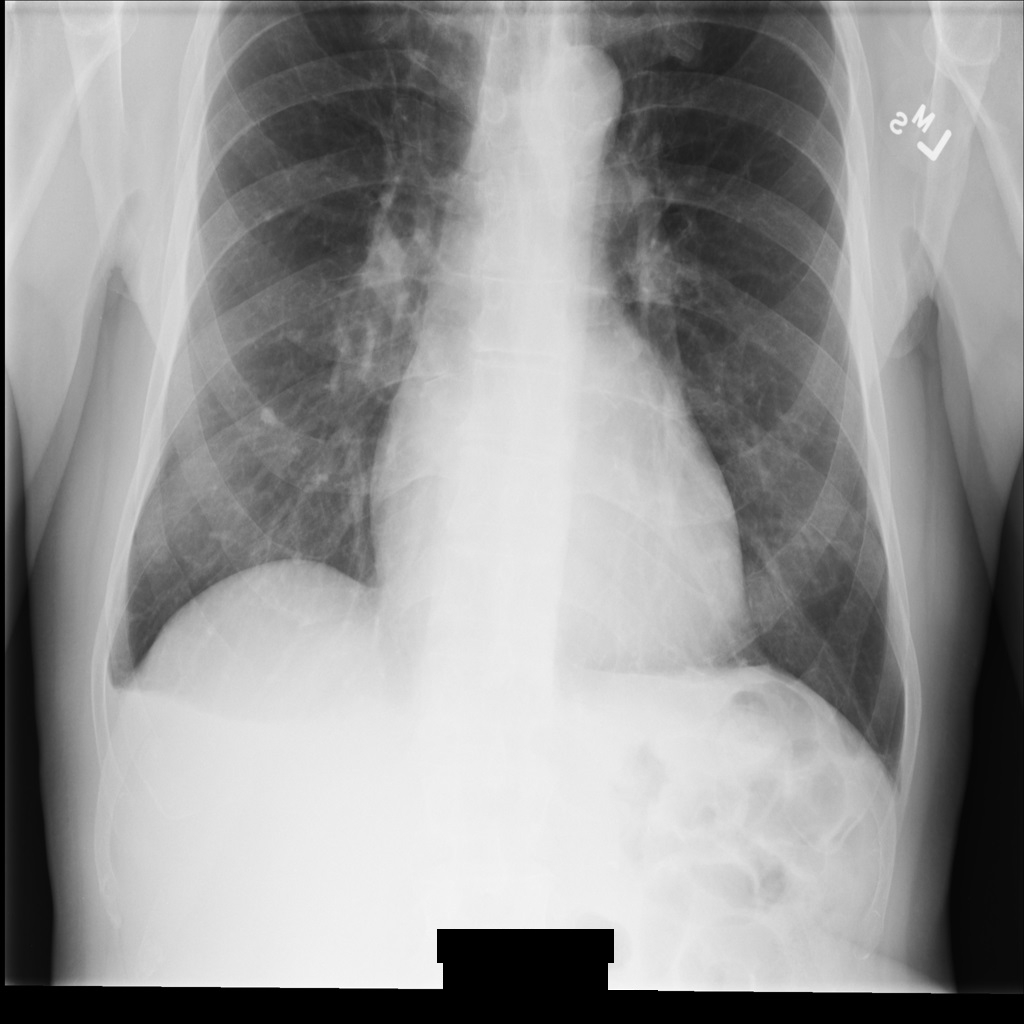

Sample image

Some samples in this page contain an output of the de-identified image. Each sample uses the following original image as its input. You can compare the output image from each de-identification operation to this original image to see the effects of the operation: